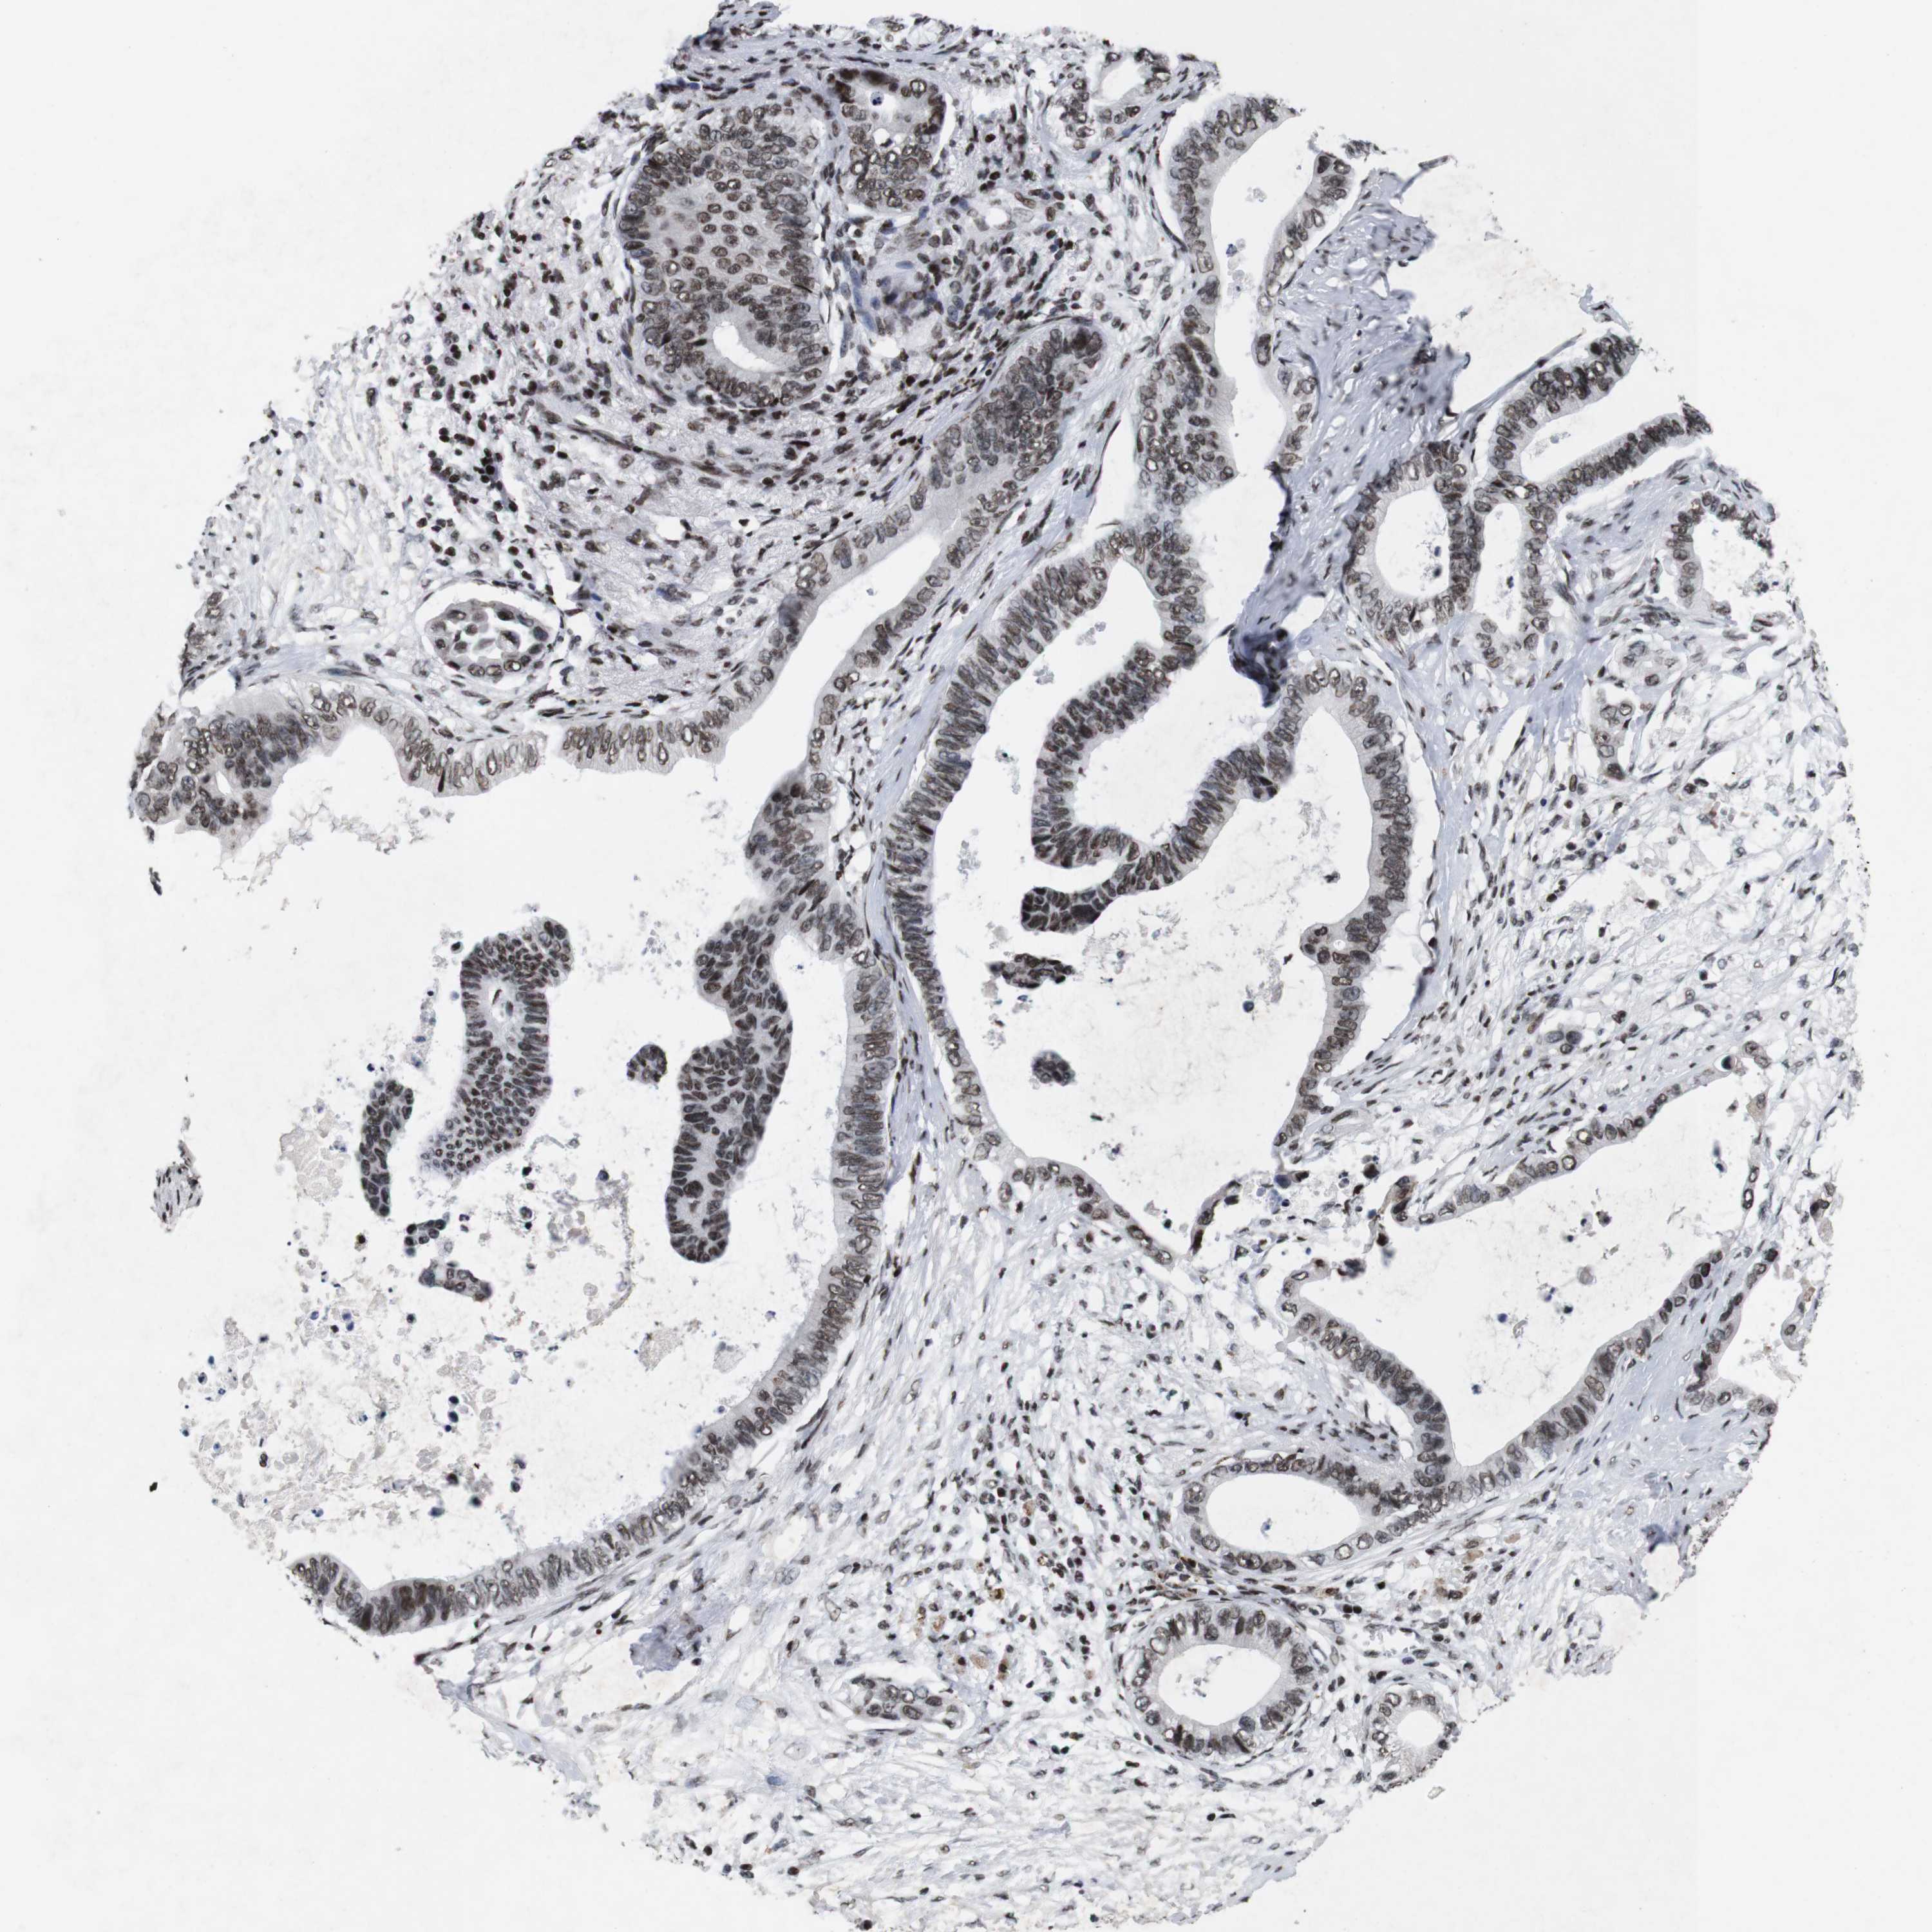

PANCREATIC CANCER - Protein expressioni

A mouse-over function shows sample information and annotation data. Click on an image to view it in a full screen mode. Samples can be filtered based on level of antibody staining by selecting one or several of the following categories: high, medium, low and not detected. The assay and annotation is described here.

Note that samples used for immunohistochemistry by the Human Protein Atlas do not correspond to samples in the TCGA dataset.

Antibody stainingi

Antibody staining in the annotated cell types in the current human tissue is reported as not detected, low, medium, or high, based on conventional immunohistochemistry profiling in selected tissues. This score is based on the combination of the staining intensity and fraction of stained cells.

Each image is clickable and will lead to virtual microscopy that enables deeper exploration of all samples and also displays staining intensity scores, fraction scores and subcellular localization as well as patient and tissue information for each sample.

Antibody HPA011324

Staining

High

Medium

Low

Not detected

Intensity

Strong

Moderate

Weak

Negative

Quantity

>75%

75%-25%

<25%

None

Location

Nuclear

Cytoplasmic/membranous

Cytoplasmic/membranous,nuclear

Adenocarcinoma, NOS